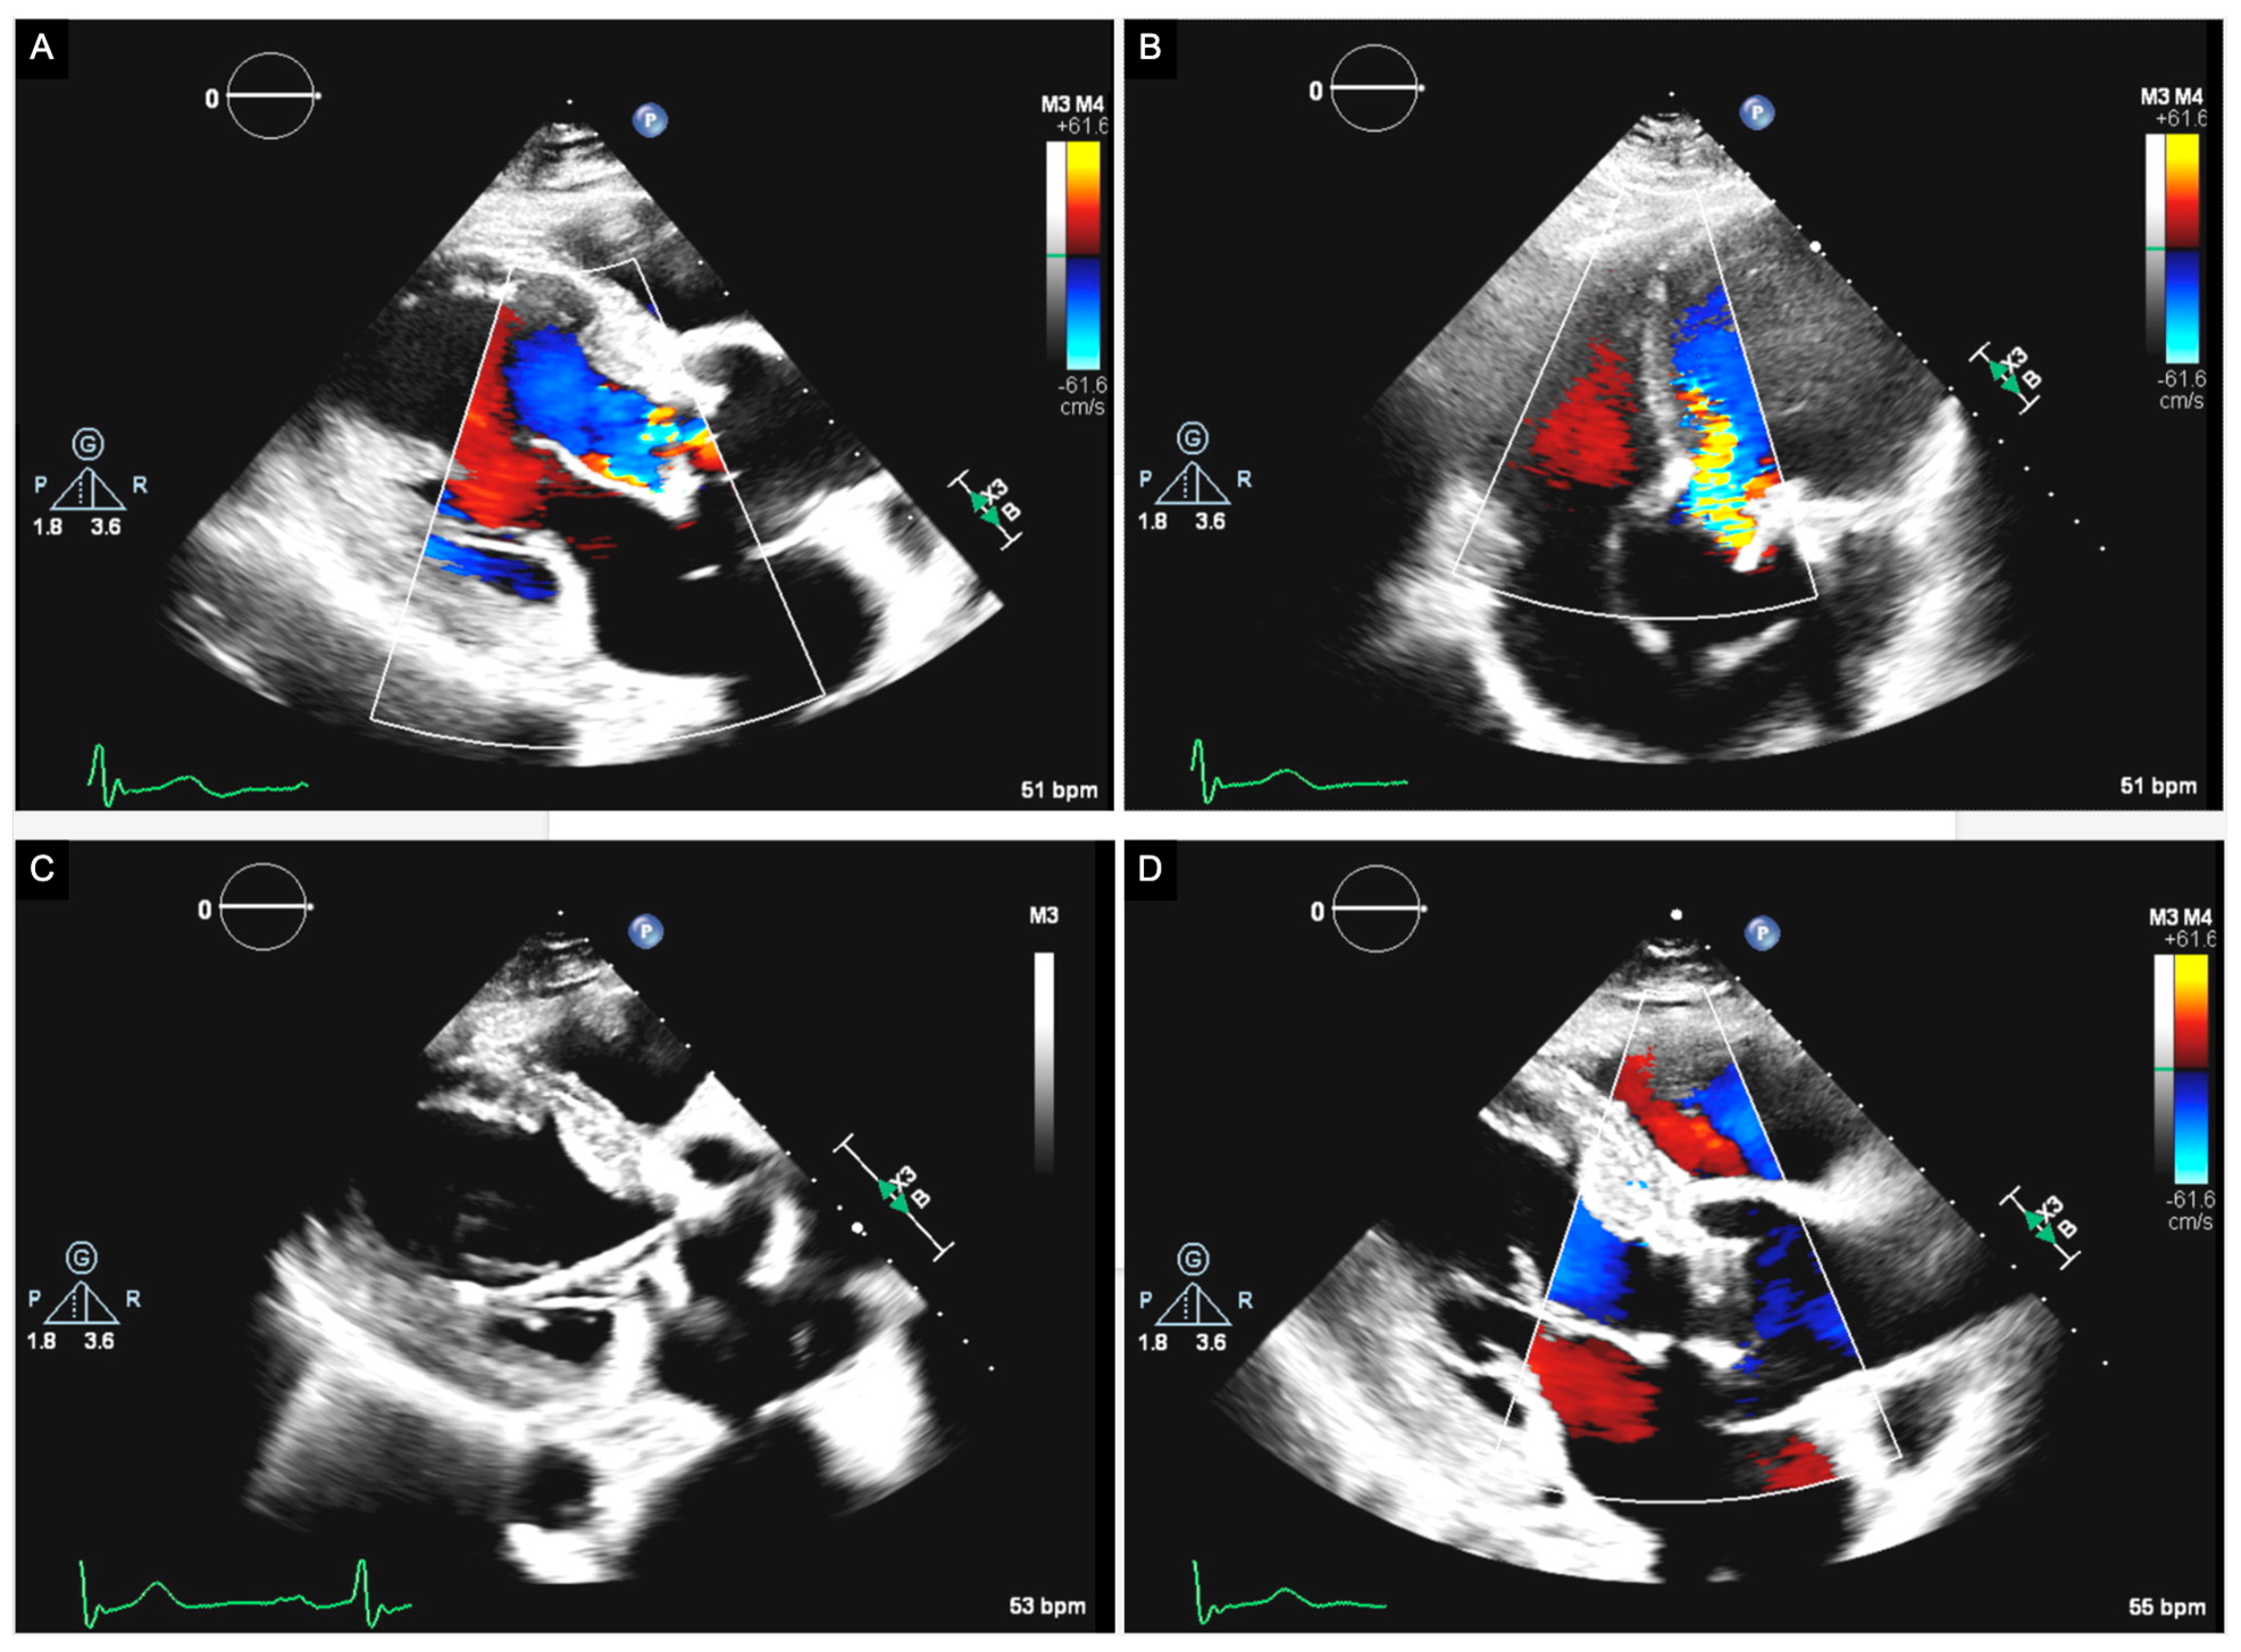

- Mirsadraee, S.; Sellers, S.; Duncan, A.; Hamadanchi, A.; Gorog, D.A. Bioprosthetic valve thrombosis and degeneration following transcatheter aortic valve implantation (TAVI). Clin. Radiol. 2021, 76, 73.e39–73.e47. [Google Scholar] [CrossRef]

- Andrews, J.P.M.; Cartlidge, T.R.; Dweck, M.R.; Moss, A.J. Cardiac CT in prosthetic aortic valve complications. Br. J. Radiol. 2019, 92, 20180237. [Google Scholar] [CrossRef] [PubMed]

- Sellers, S.L.; Blanke, P.; Leipsic, J.A. Bioprosthetic Heart Valve Degeneration and Dysfunction: Focus on Mechanisms and Multidisciplinary Imaging Considerations. Radiol. Cardiothorac. Imaging 2019, 1, e190004. [Google Scholar] [CrossRef] [PubMed]